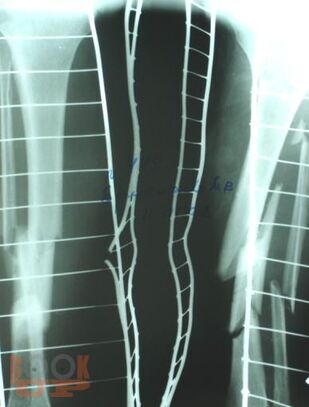

Учебное пособие содержит необходимую информацию для врачей по вопросам оказания специализированной помощи пострадавшим с тяжелой травмой костей нижних конечностей. Подробно освещены вопросы патогенеза шока как основной причины развития травматической болезни, а также тактики оказания специализированной и высоко квалифицированной помощи пострадавшим с тяжелыми монолокальными и множественными переломами костей нижних конечностей в зависимости от периода развития травматической болезни. Особое внимание уделено профилактике и лечению ранних осложнений тяжелых переломов костей нижних конечностей – синдрому жировой эмболии, тромбоэмболическим осложнениям. В пособии обобщен более чем 30- летний опыт лечения пациентов с тяжелой травмой костей нижних конечностей.